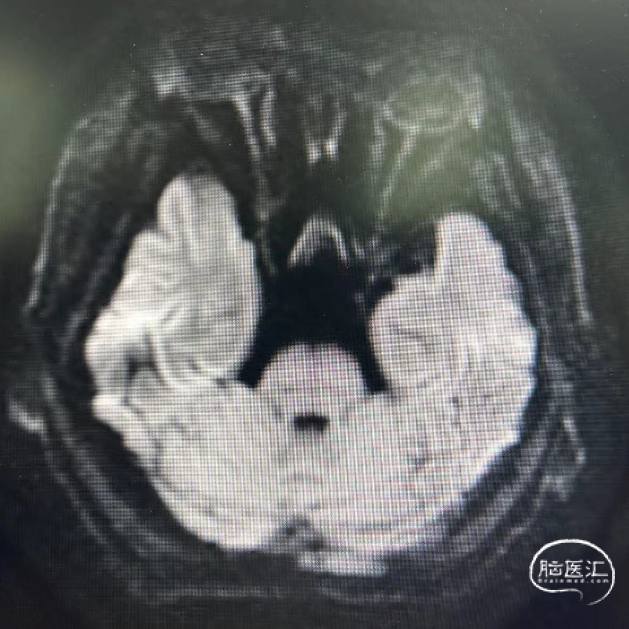

术前核磁弥散检查:未见明显高信号

经桡复查DAS造影示:左侧颈内动脉支架良好、未见内膜增生等再狭窄,左侧椎动脉起始处支架内再狭窄(重度)